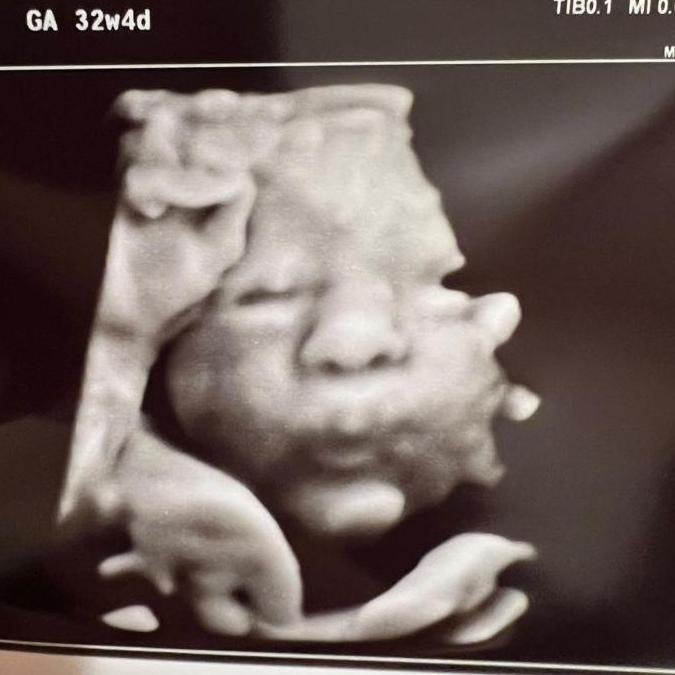

Nicolas Corlett

Ring Bearer

Although our nephew Nico hasn't arrived earth side yet, we couldn't tie the knot without crowning him our honorary ring bearer. Our baby boy is set to arrive 3 weeks before wedding day, and we cant wait to meet him! He will be joining the ceremony via zoom in the comfort of his bassinet with a bottle in hand. Pros: our first nephew whom we love so much, endless babysitting opportunities for tia Kitty and tio Gonza Cons: Too soon to tell if he has any ;)